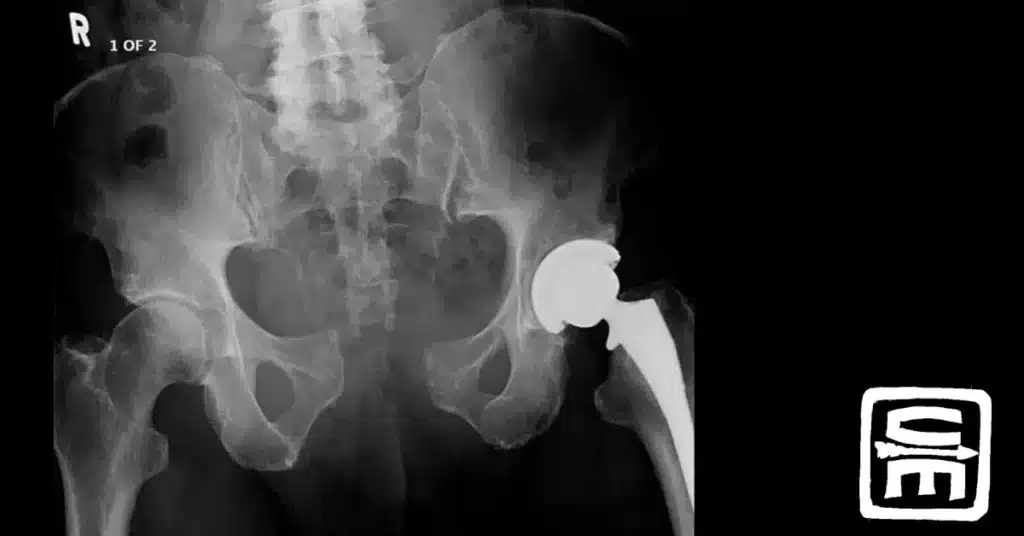

IED induced injuries resulting in traumatic lower limb amputation are associated with a 22% rate of pelvic fracture; half of which are unstable ring fractures. Death from pelvic fracture largely occurs from venous bleeding inside the pelvis.

Using a technique very similar to our improvised pant leg tourniquet, Loftus and colleges recently compared an improvised pelvis binder made from the casualty’s pants to a commercial TPOD pelvic binder in an unstable pelvic fracture model. Measuring the intrapelvic pressure in six unembalmed cadavers, they found the improvised technique resulted in similar mean and median pressures compared to the TPOD. Although not necessarily robust evidence of effectiveness, it is proof of concept.